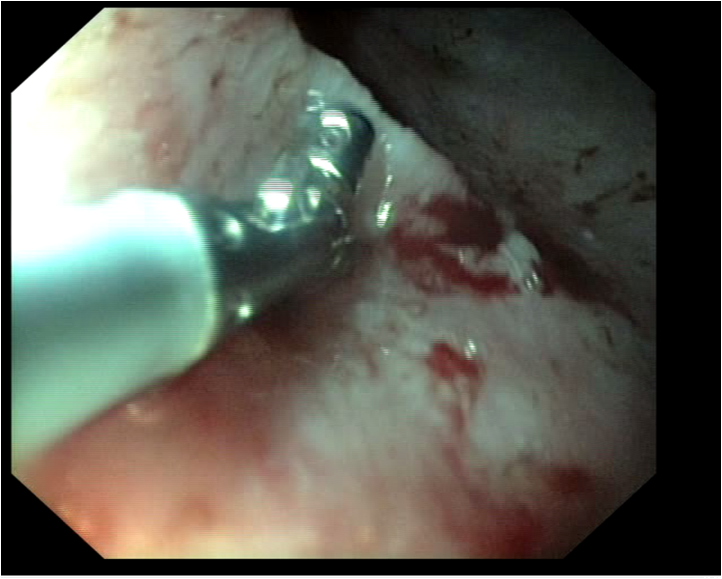

Lorsque les glandes surrénales sont fortement stimulées, elles deviennent progressivement hyperplasiques puis tumorales (tumeur bénigne puis maligne). Le diagnostic peut être établi par échographie, réalisée par un vétérinaire expérimenté avec les furets, et par une prise de sang (dosage des hormones en question). Suivant l'extension et la présence ou non d'embole vasculaire, il est recommandé de poser un implant hormonal ou de réaliser une surrénalectomie. Cette chirurgie est particulièrement risquée à cause de la proximité des glandes surrénales avec l'aorte, un vaisseau sanguin vital pour l'organisme. Il peut être utile d'utiliser des outils de microchirurgie ainsi que du matériel de pointe tel qu'une caméra endoscopique per-opératoire Vitum pour maximiser la réussite de la chirurgie.